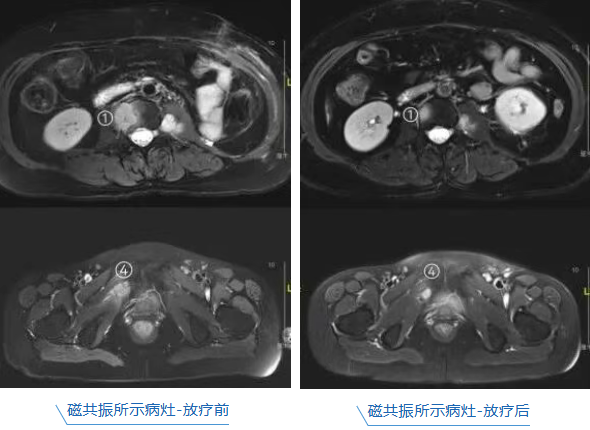

第三次放疗后,王阿姨疼痛明显减轻,夜间已能安睡。完成全部治疗后,她终于可以自信地挺直了腰板,安心出院了。目前,其病情已得到有效控制,后续团队将根据复查情况,继续优化药物治疗方案。

肿瘤六科罗敬副主任医师指出,约七成晚期肿瘤患者会发生骨转移及相关疼痛,但癌痛绝不是必须忍受的,现代精准放疗能快速缓解疼痛,降低骨折风险,显著提升患者的生活质量与尊严。